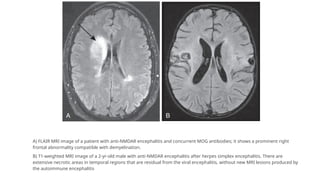

MRI BRAIN

● U/L or B/L T2/FLAIR hyperintensities involving mesial temporal lobe, hippocampal, cerebellar and

cerebral cortex

● Hyperintensities may be seen throughout brain

● Meningeal enhancement may be seen rarely

● Cortical enhancement in absence of restricted diffusion

● PET scan can highlight involvement of mesial temporal lobes

● Normal in 50-60%

A) FLAIR MRI image of a patient with anti-NMDAR encephalitis and concurrent MOG antibodies; it shows a prominent right

frontal abnormality compatible with demyelination.

B) T1-weighted MRI image of a 2-yr-old male with anti-NMDAR encephalitis after herpes simplex encephalitis. There are

extensive necrotic areas in temporal regions that are residual from the viral encephalitis, without new MRI lesions produced by

the autoimmune encephalitis